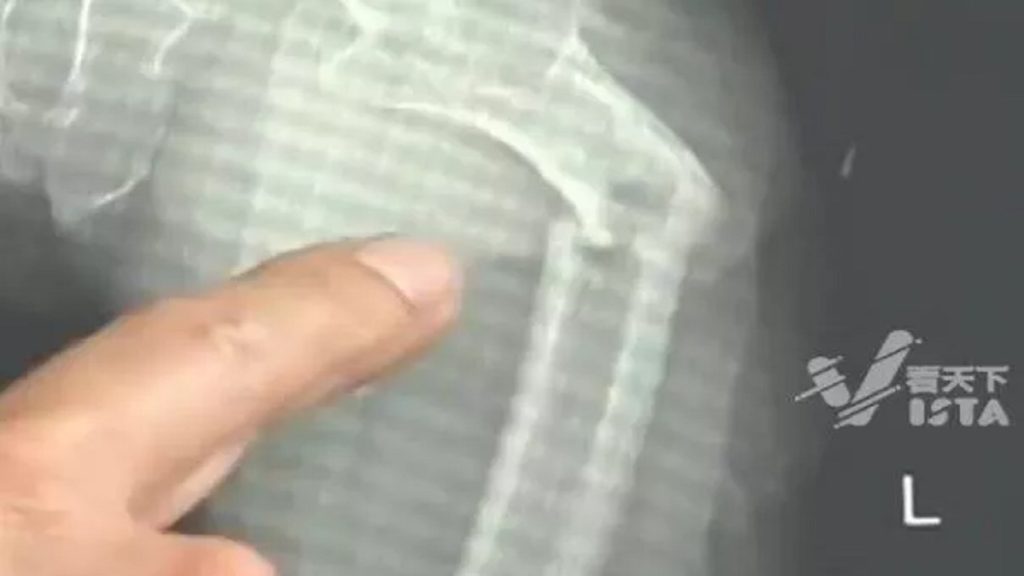

وأظهرت الأشعة السينية أن «يي» عانى من كسر في عظمة الفخذ، لكن قصته عن السعال لم تكن منطقية، ولم تكن هناك أي علامة على وجود أي صدمة جسدية، فقرر الأطباء إجراء مزيد من التحقيق، وسألوا المريض عن صحته العامة وعاداته الغذائية وأسلوب حياته، كما أجروا أيضاً اختبار كثافة العظام الذي أدى إلى نتائج مثيرة للقلق.

وقال الموقع الإخباري الصني إن كثافة عظام المريض كانت مماثلة لكثافة عظام رجل يبلغ من العمر 80 عاماً، وهو أمر غير معتاد، حتى بالنسبة للرجال المعاصرين قليلي الحركة.

وحين تبين أن «يي» لا يعاني من أي أمراض في العظام، خلص الأطباء إلى أن عظامه كانت هشة بشكل لا يصدق نتيجة لعاداته في شرب المشروبات الغازية، وسوء التغذية، وعدم ممارسة الرياضة.